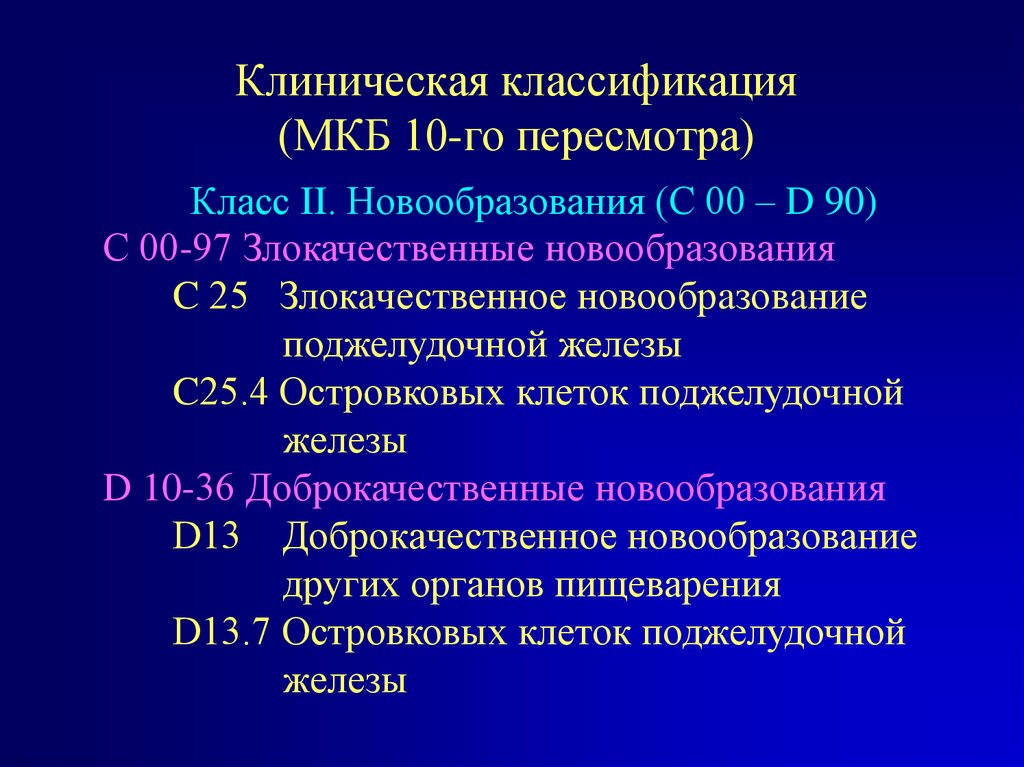

Код мкб 10 атерома головы

Код мкб 10 атерома головы 109 фото